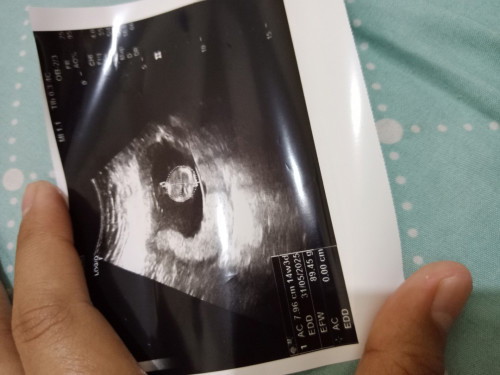

Sharing dong 3 bulan 5 hari Apakah ini normal??Klu liat usg yg lain kok besar ya kehamilan 3 bulan

waktu saya USG usia 8w juga keliatan bulet kecil tapi hasil USG orang lain udah pada mulai keliatan terpisah kepala perut sama kakinya

Iyaa biasanya kalau 14w udh keliatan janinnya agak besar. Dokternya gak bilang apa2 bun?

itu yang di print bagian kepala aja bun Klo baca dari hsilnya bagus kok itu sesuai usia ukuran dede nya

itu kayanya yg di print foto USG bagian kepala bun. bukan keseluruhan badan janin

CRL nya berapa Bun soalnya USG pertama ku sama 3 bulan 5 hari juga

maaf bunda itu kaya 10 minggu waktu aku dlu segede itu

Tergantung sih kak, kadang keliatan gede/engga nya karna di zoom sama dokternya

Itu usg bagian kepala ya bun?